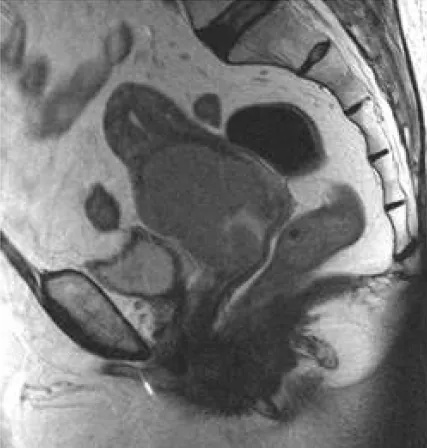

【108-1 醫學(六) 第73題】68歲女性病患,已停經,主訴不正常陰道出⾎,磁振造影檢查如下圖。其最可能的診斷為何?

詳解

破題關鍵

這張磁振造影(MRI)影像清楚顯示在子宮頸區域有一個巨大的、不規則的腫塊,並向下延伸侵犯到陰道,這在一位停經後有不正常陰道出血的68歲女性身上,最符合子宮頸癌的表現。